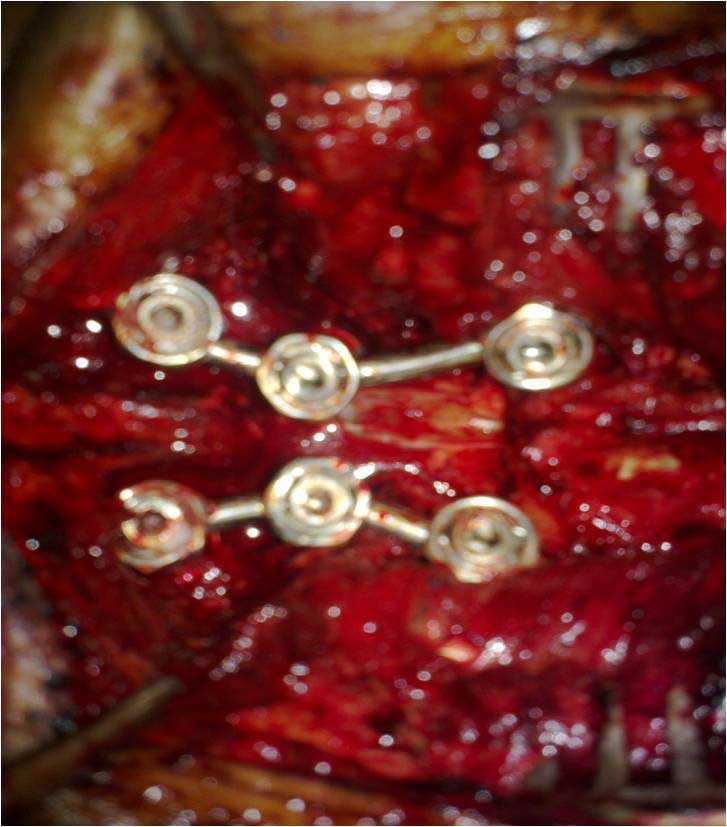

DORSAL SPINE FIXATION INTRA OP

Spine Fixation Lumbar Spine